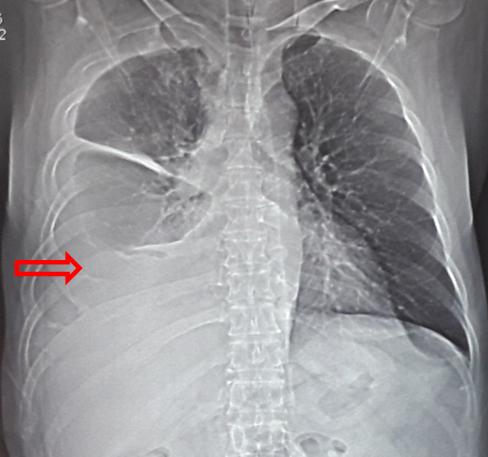

-       Chụp cộng hưởng từ sọ não: u não thùy trán đỉnh phải phải, kích thước 35 x 45mm, ngấm thuốc dạng viền, phù não xung quanh, nghĩ tới tổn thương thứ phát.

Hình 2: Hình ảnh chụp cộng hưởng từ sọ não trước điều trị (vòng tròn đỏ: u não thùy trán đỉnh phải, kích thước 35 x 45mm, ngấm thuốc dạng viền, phù não xung quanh)